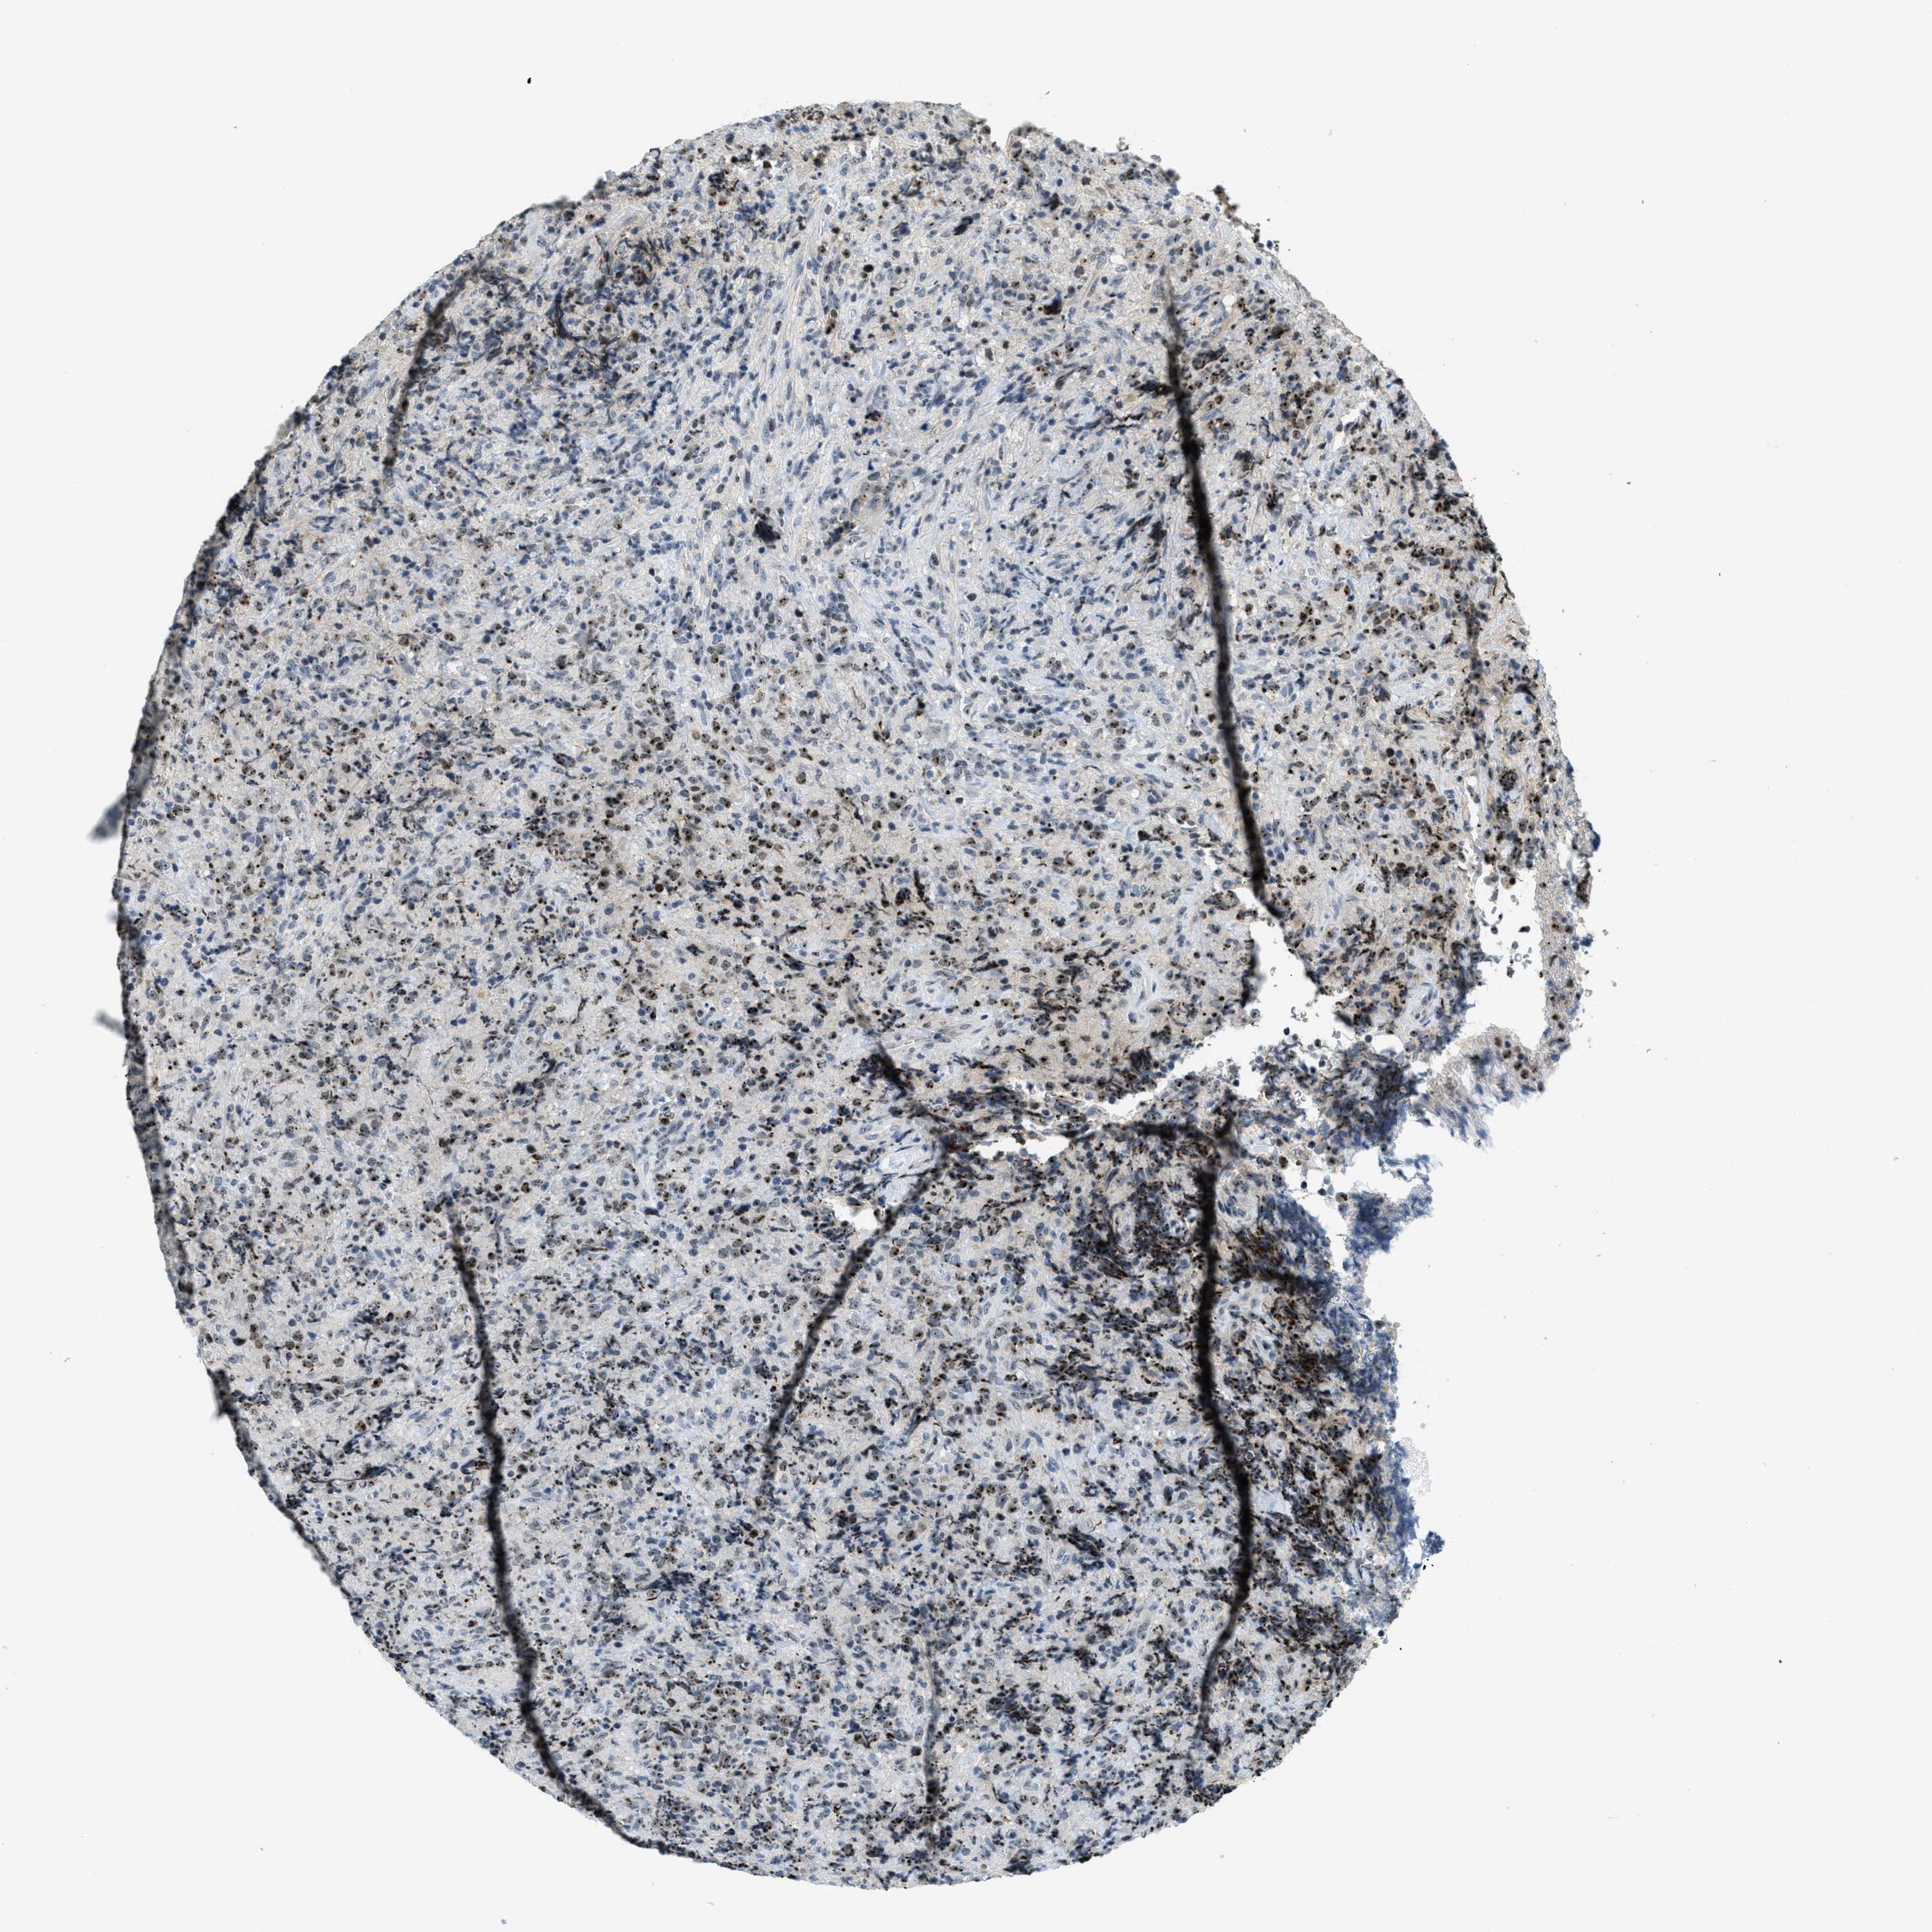

CANCER LYMPHOMA Show tissue menu

LYMPHOMA - Protein expressioni

A mouse-over function shows sample information and annotation data. Click on an image to view it in a full screen mode. Samples can be filtered based on level of antibody staining by selecting one or several of the following categories: high, medium, low and not detected. The assay and annotation is described here.

Each image is clickable and will lead to virtual microscopy that enables deeper exploration of all samples and also displays staining intensity scores, fraction scores and subcellular localization as well as patient and tissue information for each sample.

Antibody HPA014855

Staining

High

Medium

Low

Not detected

Intensity

Strong

Moderate

Weak

Negative

Quantity

>75%

75%-25%

<25%

None

Location

Nuclear

Cytoplasmic/membranous

Cytoplasmic/membranous,nuclear

Hodgkin's disease, NOS

Malignant lymphoma, non-Hodgkin's type, High grade

Malignant lymphoma, non-Hodgkin's type, Low grade